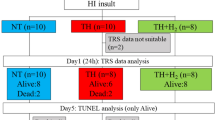

After a 40-min insult and resuscitation, 36 piglets ≤24 h old were divided into three groups: normothermia (NT, n = 14), TH alone (33.5 ± 0.5 °C, 24 h, n = 13), and TH + H2 (2.1–2.7% H2 gas, 24 h, n = 9). aEEG was recorded for 24 h post-insult and its background pattern, status epilepticus (SE; recurrent seizures lasting >5 min), and seizure occurrence (Sz; occurring at least once but not fitting the definition of SE) were evaluated. Background findings with a continuous low voltage and burst suppression were considered abnormal.

Thirty-six newborn piglets (Camborough; Daiwa Chikusan, Kagawa, Japan) within 24 h of birth and weighing 1.5–2.1 kg were obtained for the study and divided into the three treatment groups: HI insult treated with NT (NT group, n = 14), HI insult treated with TH (TH group, n = 13), and HI insult treated with TH and H2 gas ventilation (TH + H2 group, n = 9).

Piglets were assigned to the NT (n = 14), TH (n = 13), or TH + H2 (n = 9) groups. Within 24 h after insult, all piglets in the NT and TH + H2 groups had survived, but one piglet had died in the TH group. Thus, aEEG analysis was performed in 14 piglets in the NT group, 12 piglets in the TH group, and 9 piglets in the TH + H2 group.

The mean ± SD body weights were 1768 ± 128 g in the NT group, 1794 ± 174 g in the TH group, and 1829 ± 204 g in the TH + H2 group. At 24 h after insult, all piglets were alive in the NT group (n = 14; 6 males and 8 females), all were alive in the TH group except one (12 of 13; 11 males and 2 females), and all were alive in the TH + H2 group (n = 9; 6 males and 3 females; Fig. 2).